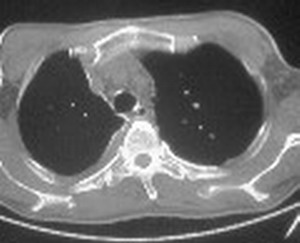

标题: CT6943:[讨论]胸部,M/67Y,体检发现。

ct值约12hu。

ct值约12hu